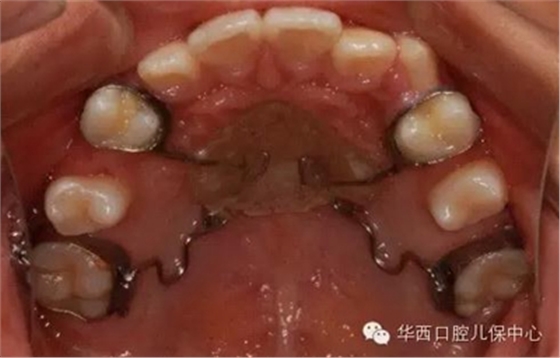

或使用擺式矯治器推磨牙遠(yuǎn)中等

圖為幾種活動(dòng)擴(kuò)弓矯治器的設(shè)計(jì)